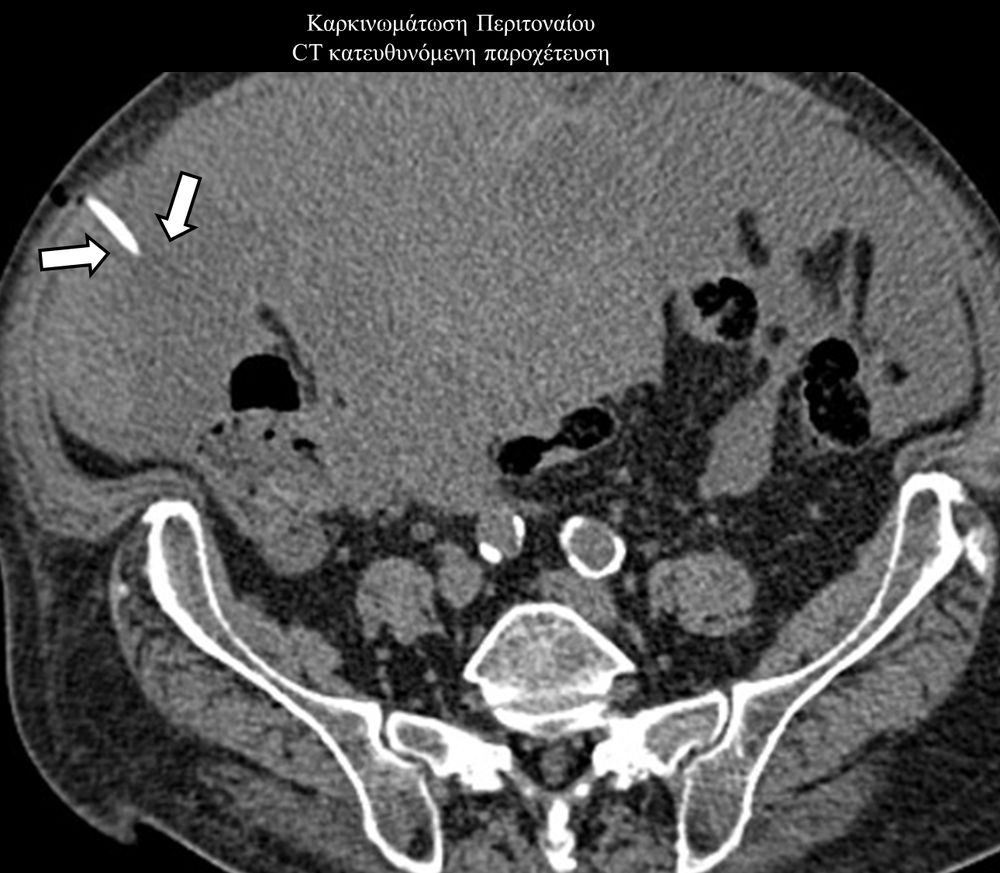

Η παρέμβαση διενεργείται υπό την καθοδήγηση αξονικού τομογράφου ή υπερήχων ή και με συνδυασμό τους. Ο επεμβατικός ακτινολόγος αρχικά αναισθητοποιεί την ανατομική περιοχή ενδιαφέροντος με τη χρήση τοπικής αναισθησίας και παρακεντεί την συλλογή διαδερμικά με λεπτή βελόνη. Στη συνέχεια μέσω ομοαξονικών συστημάτων συρμάτων-καθετήρων-διαστολέωντοποθετείται διαδερμικός καθετήρας τύπου pig-tail εντός της συλλογής, ο οποίος συνδέεται με εξωτερική παροχέτευση.